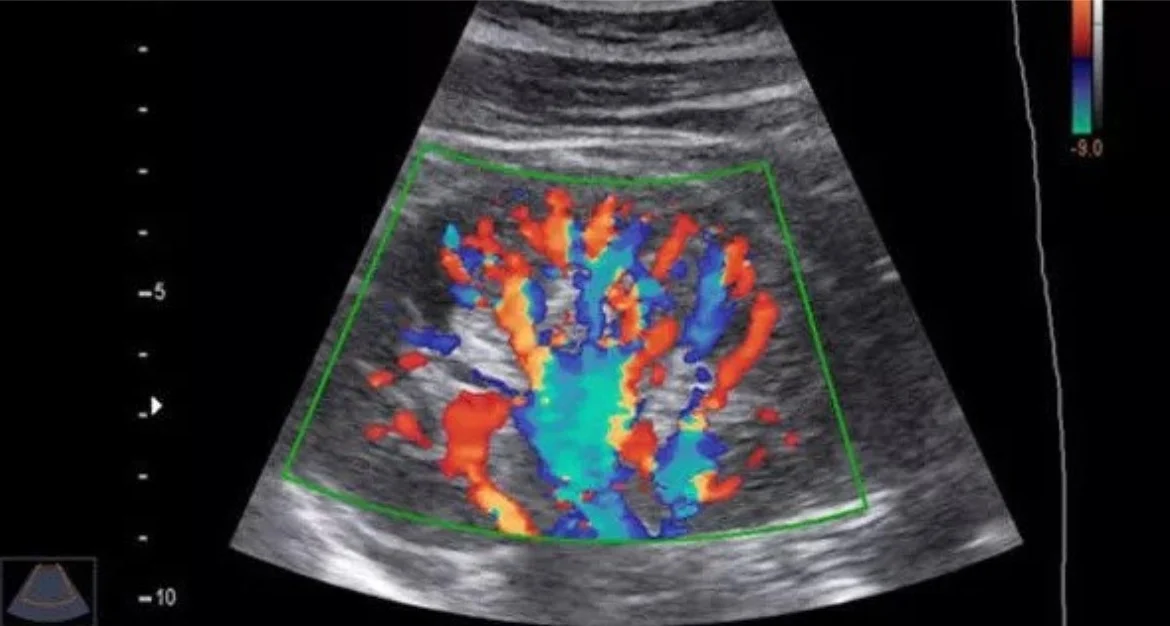

The Colour Doppler sonography is a kind of ultrasound technique. It helps to see how blood is moving in the Colour Doppler sonography. This technique looks at the blood flow in the veins and arteries.

The Colour Doppler sonography is different from an ultrasound. The Colour Doppler sonography shows which way the blood is going how fast it is moving and what the pattern of the blood movement is. This information from the Colour Doppler sonography helps the doctors find any blockages in the blood vessels or if the blood vessels are too narrow or if there are problems, with the valves or if the blood is not circulating properly with the help of Colour Doppler sonography.

Colour Doppler sonography is used for things. It is a type of ultrasound test. Colour Doppler sonography helps doctors see blood flowing through the blood vessels. Doctors use Colour Doppler sonography to check the blood vessels. They use Colour Doppler sonography to see if the blood vessels are working properly. Colour Doppler sonography is very helpful. Doctors like to use Colour Doppler sonography because it helps them find problems, with the blood vessels. Doctors use Colour Doppler sonography to look at the blood flow in the arteries and the veins. This helps them find out if there are any problems with the blood circulation.

Colour Doppler sonography can detect things like blocked vessels or varicose veins. It can also find blood clots. See if the organs and the limbs are getting enough blood supply from the Colour Doppler sonography. The Colour Doppler sonography is very useful for the doctors to figure out what is going on with the blood flow, in the arteries and the veins.

Yes. A normal ultrasound is really good at showing what the organs and tissues look like.. Colour Doppler does that and also shows where the blood is going and how fast it is moving. This makes Colour Doppler really useful for problems with the blood vessels and the way the blood circulates in the body. Colour Doppler is especially helpful, for people who have problems or issues with their circulation.